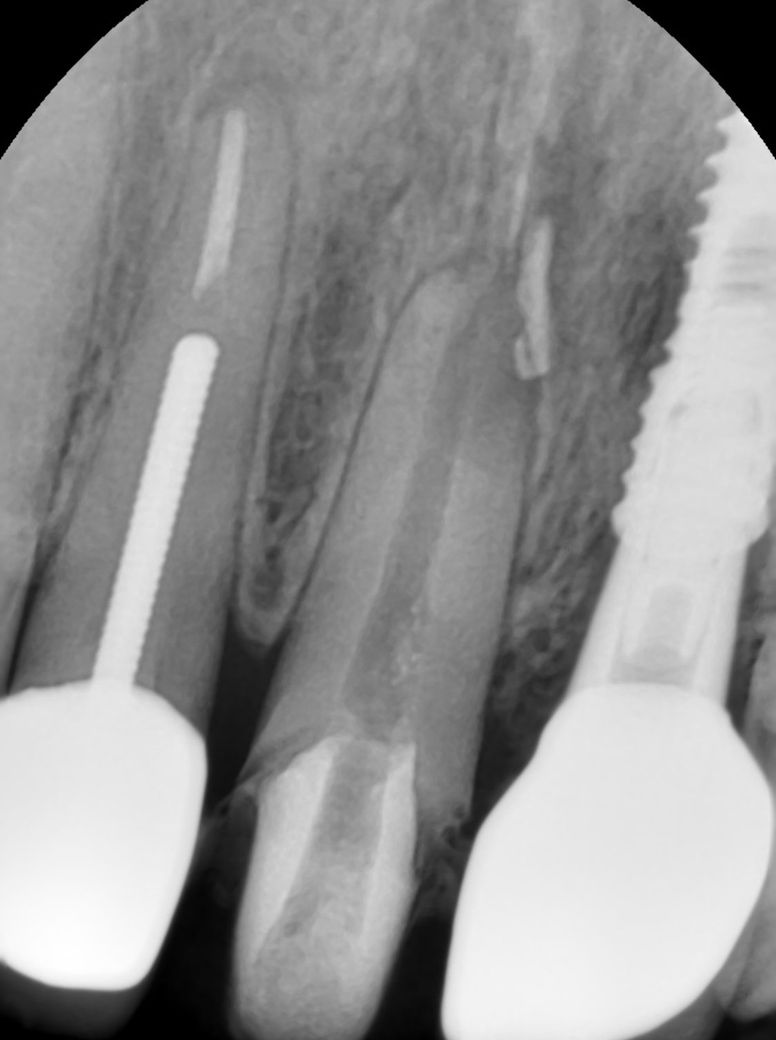

사진 첨부합니다 해당 치아는 임플란트 옆에 앞니입니다

사진상으로는 염증이 그렇게 심한거 같지 않는거 같습니다. 발치하시고 염증을 충분히 긁어내고 임플란트 심어도 크게 문제가 되진 않을것같습니다.

정확히 보기위해선 씨티 사진이 필요합니다.

파노라마만 봐서는 정확히 판단하긴 어렵습니다.

보통 앞니는 심미적인 부위이기 때문에 웬만해서는 발치즉시 식립을 하게되지만, 염증이 너무 심하다면 발치후 기다렸다가 심는게 좋습니다. 감사합니다.